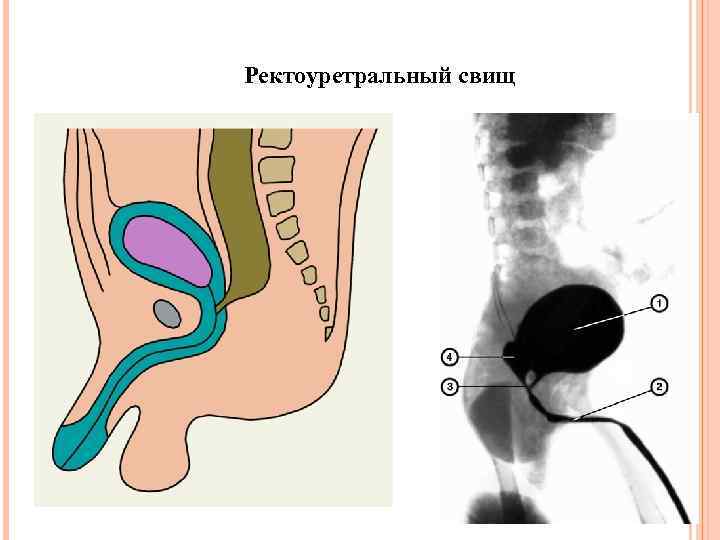

Ректоуретральный свищ

Ректоуретральный свищ